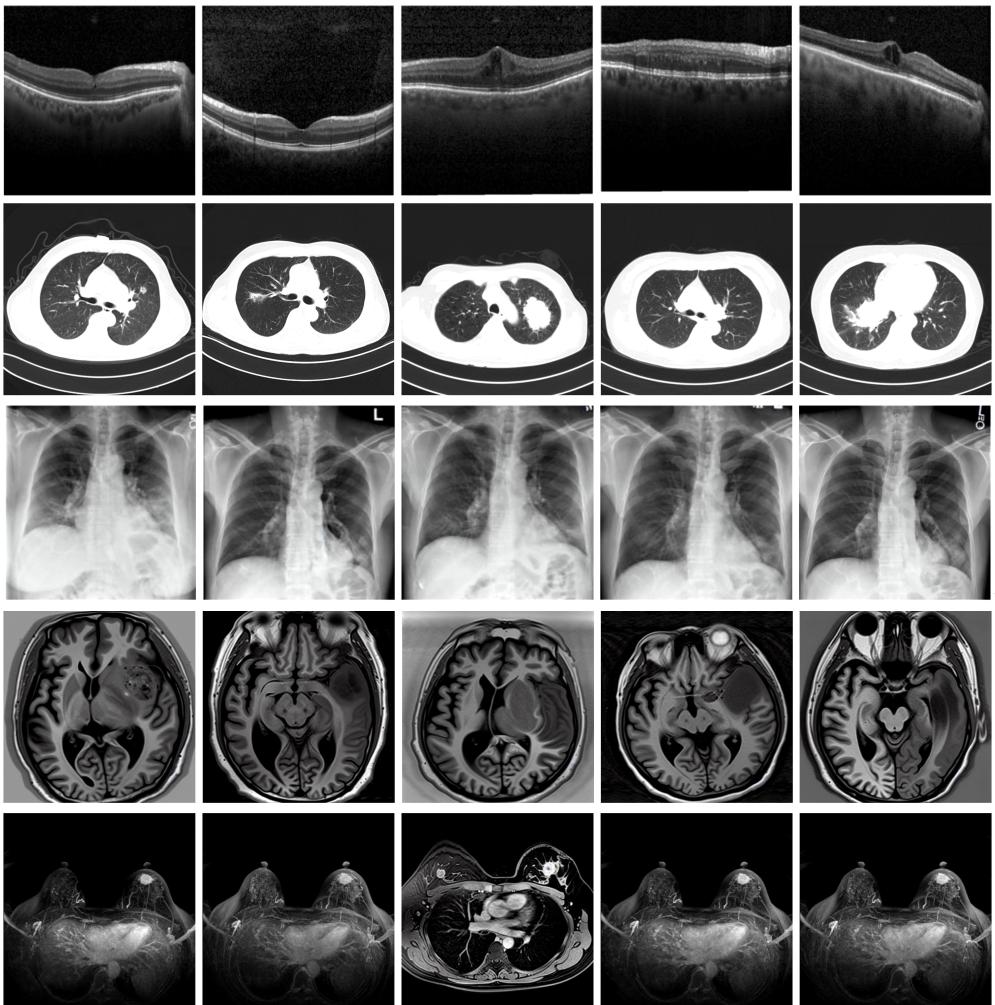

圖為由MINIM生成的高質(zhì)量醫(yī)學(xué)合成圖像(受訪者供圖)

“目前公開(kāi)的醫(yī)學(xué)影像數(shù)據(jù)非常有限,我們建立的生成式模型有望解決訓(xùn)練數(shù)據(jù)不夠的問(wèn)題?!北本┐髮W(xué)未來(lái)技術(shù)學(xué)院助理研究員王勁卓說(shuō),研究團(tuán)隊(duì)利用多種器官在CT、X光、磁共振等不同成像方式下的高質(zhì)量影像文本配對(duì)數(shù)據(jù)進(jìn)行訓(xùn)練,最終生成海量的醫(yī)學(xué)合成影像,其在圖像特征、細(xì)節(jié)呈現(xiàn)等多方面都與真實(shí)醫(yī)學(xué)圖像高度一致。

實(shí)驗(yàn)結(jié)果顯示,MINIM生成的合成數(shù)據(jù)在醫(yī)生主觀評(píng)測(cè)指標(biāo)和多項(xiàng)客觀檢驗(yàn)標(biāo)準(zhǔn)方面達(dá)國(guó)際領(lǐng)先水平,在臨床應(yīng)用中具有重要參考價(jià)值。在真實(shí)數(shù)據(jù)基礎(chǔ)上,使用20倍合成數(shù)據(jù)在眼科、胸科、腦科和乳腺科的多個(gè)醫(yī)學(xué)任務(wù)準(zhǔn)確率平均可提升12%至17%。